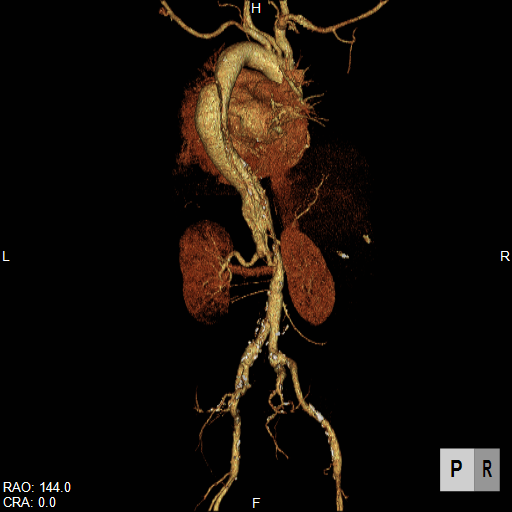

大動脈疾患の診断では、①瘤/解離の範囲と位置、②血流評価、③主要分枝・周囲臓器との関係、④並存疾患の評価、⑤ステントグラフト治療の可能性評価などが必要です。

CTは、体軸方向に分解能の高いボリュームデータを短時間かつ広範囲に得ることができるので、体軸方向に広いスキャンが必要な大動脈疾患の検査に適しています。大動脈病変と分枝動脈の関係だけでなく、分枝動脈自身の評価も可能ですから、手術前シミュレーションや、インフォームドコンセントの参照画像にも有用です。

腹部大動脈瘤へのステントグラフト内挿術評価CT